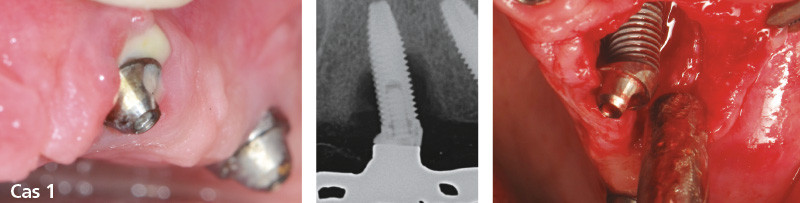

Les péri-implantites avancées : traiter ou déposer ?

Les péri-implantites sont pour la plupart asymptomatiques et le diagnostic est souvent tardif. Le praticien est donc confronté à des pertes osseuses péri-implantaires souvent sévères pouvant représenter plus de la moitié de la hauteur de l’implant. De plus, la morphologie des lésions osseuses associées peut être plus ou moins complexe.

Il est donc logique de se poser la question, face à une péri-implantite sévère, de la conservation ou de la dépose de l’implant atteint. Il n’existe aujourd’hui dans la littérature aucun arbre décisionnel concret pour cette prise de décision : traiter ou déposer ?